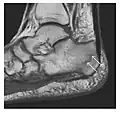

The greater tuberosity of the humerus is also an illustrative location of occult fractures. The osseous injury may follow seizures, glenohumeral dislocation, forced abduction, or direct impaction. They are commonly discovered on MRI in symptomatic patients with suspicion of rotator cuff tear. Coronal images are best suited for detection. They appear as crescentic oblique lines surrounded by a bone marrow edema pattern (Figure 5). The rotator cuff must be inspected since associated ligamentous lesions are common. In the ankle, malleoli and tarsal bones should be checked carefully for any cortical disruptions and radiolucent lines that may reveal a fracture. Awareness of the exact location of the pain will help direct the attention of the interpreter when searching for very subtle signs of fracture (Figure 6).[1]

Figure 6: Subtle anterior talar fracture in a 39-year-old man presenting with ankle pain after a fall. (a) Anteroposterior radiograph shows a subtle oblique radiolucent line through the talus (white arrows). (b) Sagittal CT reformation confirms the presence of an anterior talar fracture with cortical offset (black arrow). Avulsion fractures, which consist of a detached bone fragment resulting from a ligament or tendon pulling away from the bone, may also present with subtle radiographic signs. Tiny osseous fragments near the presumed attachment site of a ligament suggest this diagnosis. Common sites are the lateral tibial plateau (the Segond fracture), the spinal tuberosity of the tibia resulting from anterior cruciate ligament avulsion, and the ischial tuberosity.[1]